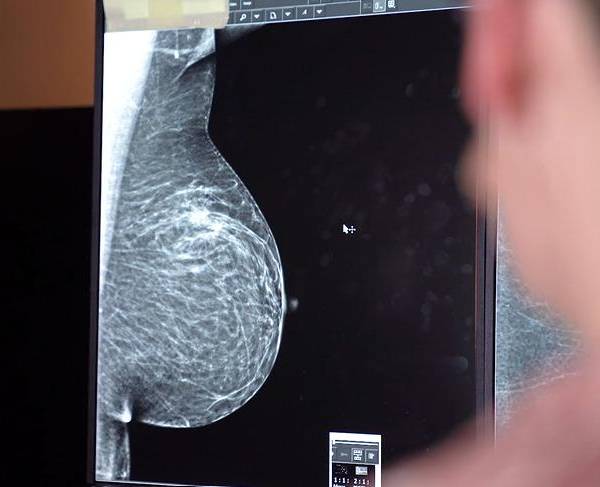

Nueva técnica permite recuperar sensibilidad tras mastectomía en pacientes con cáncer de mama

La mastectomía, aunque es un procedimiento vital para tratar el cáncer de mama, tiene impactos físicos y emocionales importantes para las mujeres.

La intervención se llevó a cabo el miércoles 18 de junio en una paciente de 52 años con diagnóstico de cáncer de mama. El enfoque principal del procedimiento fue la neuropreservación, una técnica que busca conservar la sensibilidad de la zona intervenida y, de ser posible, mantener el pezón. Esta iniciativa forma parte de un programa colaborativo entre ambas instituciones médicas.

Los médicos explicaron que, tras una mastectomía, muchas pacientes experimentan pérdida de sensibilidad o dolor crónico debido a la sección de los nervios en el área pectoral. El cirujano plástico Andrés Rivadeneira detalló que, con la técnica implementada, se identifican y preservan los nervios intercostales, que son los responsables de la sensibilidad en la zona. "Estos nervios pueden ser rastreados desde donde emergen, a nivel del músculo pectoral, y luego trasladados a la zona extirpada", indicó.